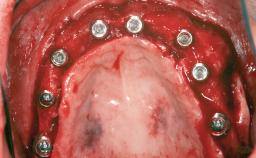

Shell Technique for Horizontal and Vertical Maxillary Bone Augmentation in a Partially Edentulous Patient with Aggressive Periodontal Disease

# of Teeth 5

# of Implants 3

Type of Implants One-Piece

Bone Augmentation Horizontal|Staged|Vertical